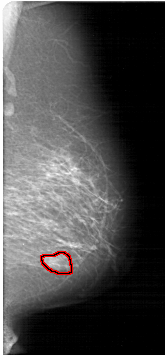

A_1371_1.LEFT_MLO

FILE: A_1371_1.RIGHT_MLO.OVERLAY

TOTAL_ABNORMALITIES 1

ABNORMALITY 1

LESION_TYPE MASS SHAPE LOBULATED MARGINS OBSCURED

ASSESSMENT 4

SUBTLETY 3

PATHOLOGY BENIGN

TOTAL_OUTLINES 1

BOUNDARY